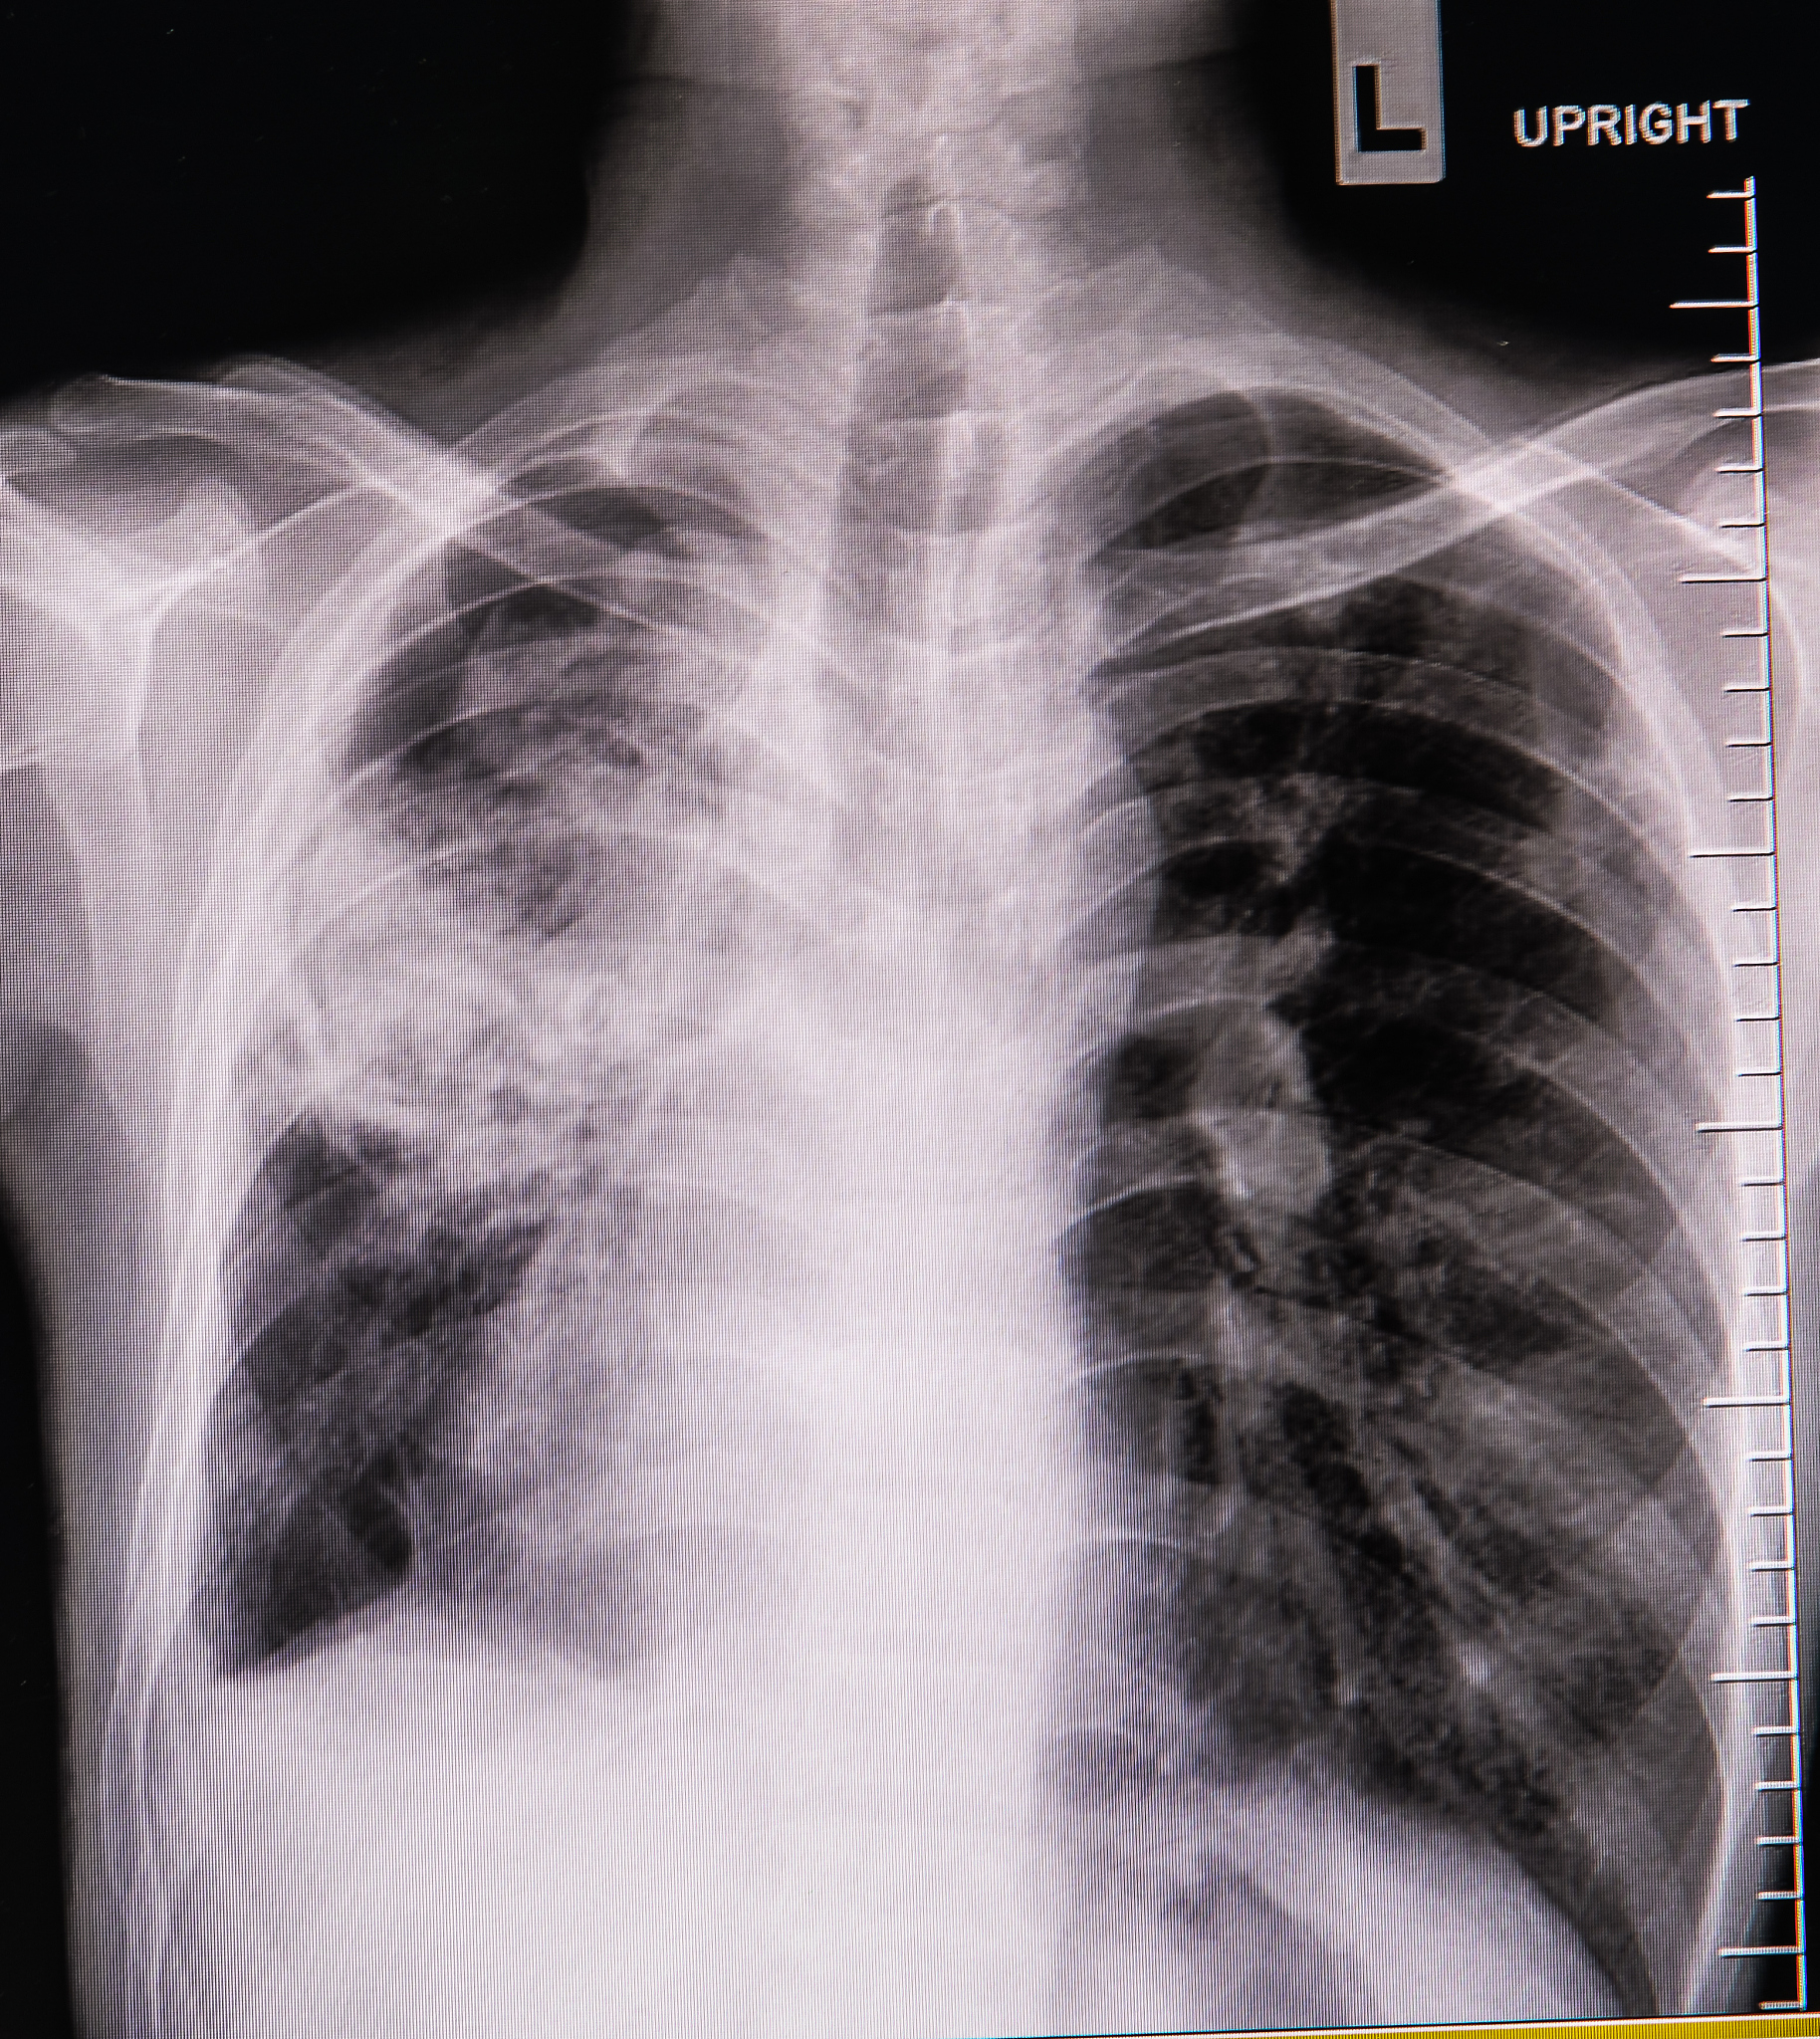

右肺腺癌术后呼吸衰竭伴肌肉脓肿感染护理指南

右肺腺癌术后出现呼吸衰竭和肌肉脓肿感染是较为严重的并发症,需要进行积极的治疗和护理。本文将为患者家属和护理人员提供详细的护理指南。